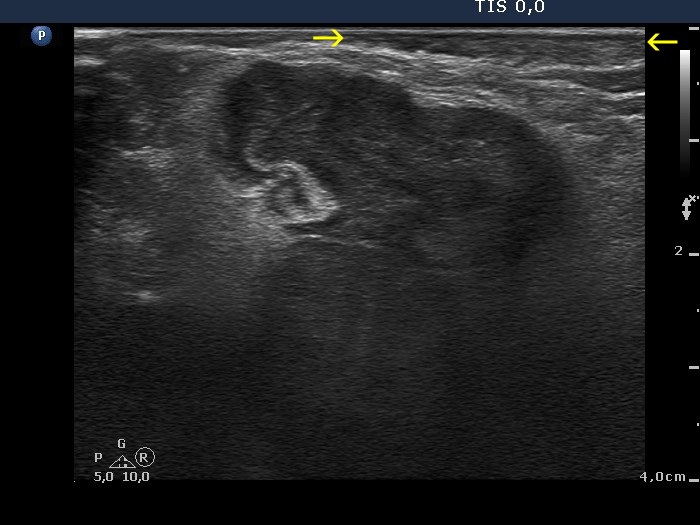

Benign hyperplastic nodules (histology) - case 1633 |

Transverse scan |

Longitudinal scan |

The lobe has multiple nodules, including hypoechoic and iso/hyperechoic lesions, as well. The hypoechoic nodule is brighter than the strap muscle, therefore this is a minimally/moderately hypoechoic lesion.